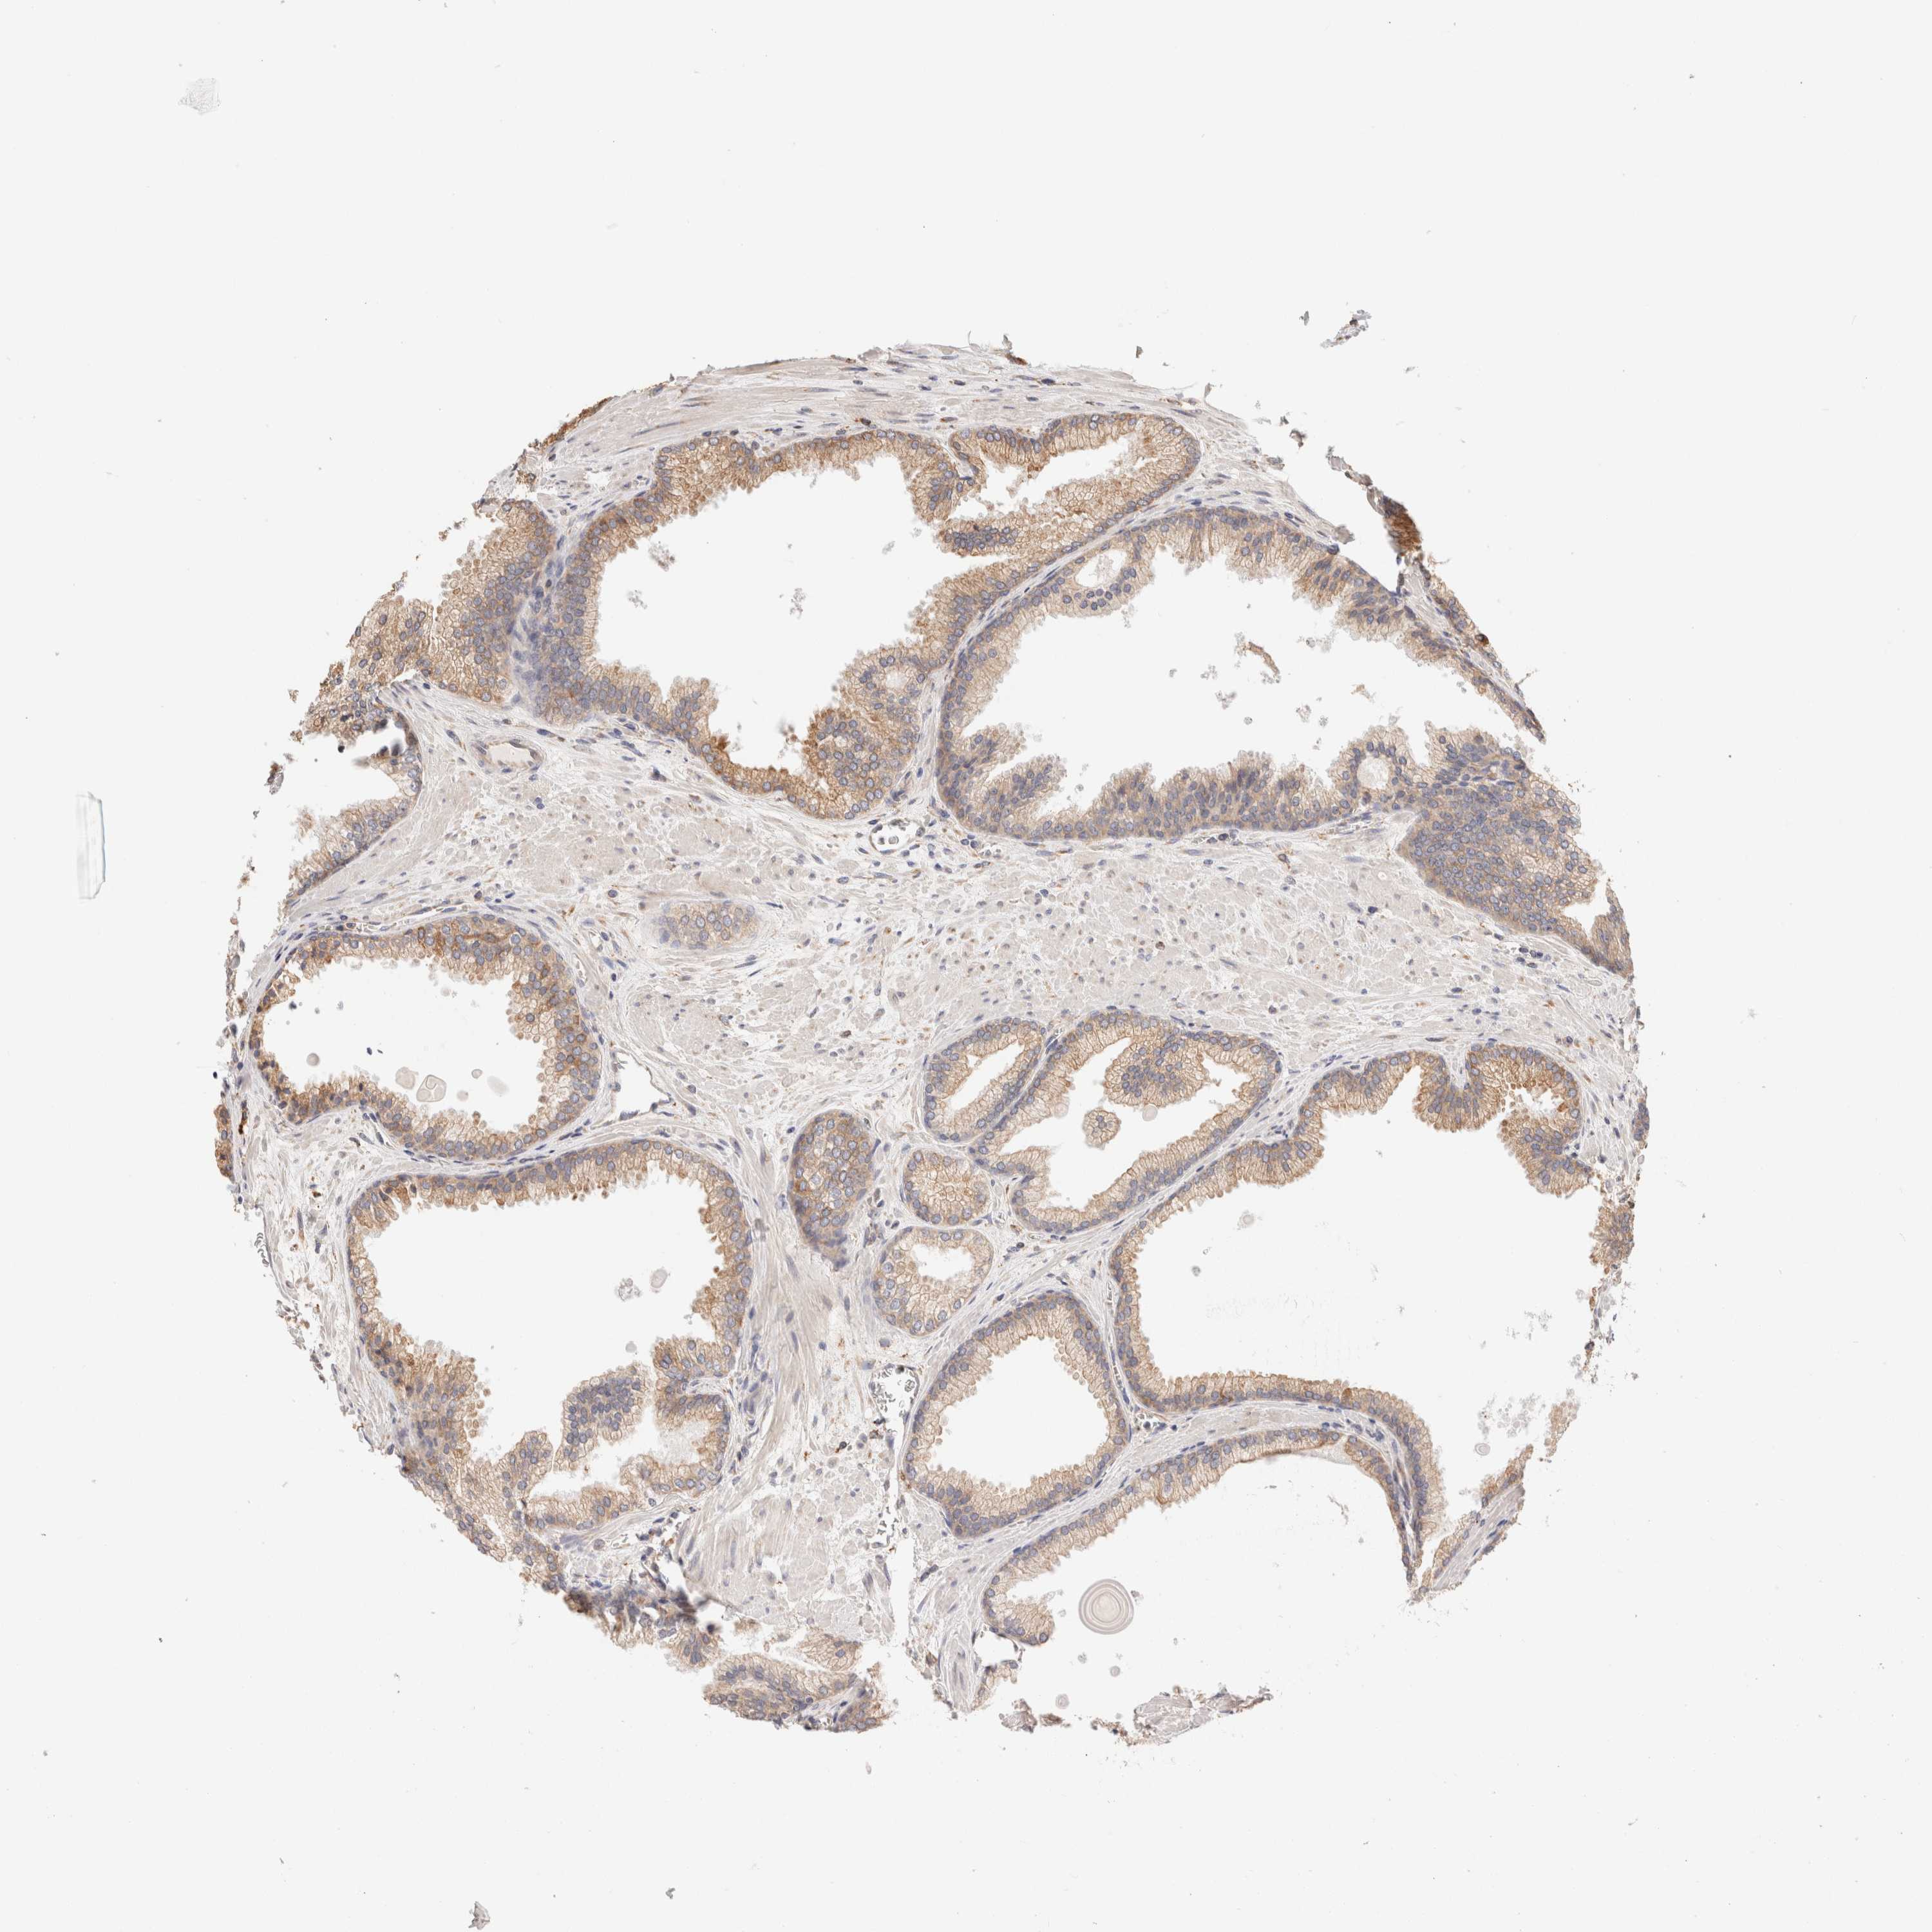

PROSTATE CANCER - Protein expressioni

A mouse-over function shows sample information and annotation data. Click on an image to view it in a full screen mode. Samples can be filtered based on level of antibody staining by selecting one or several of the following categories: high, medium, low and not detected. The assay and annotation is described here.

Antibody stainingi

Antibody staining in the annotated cell types in the current human tissue is reported as not detected, low, medium, or high, based on conventional immunohistochemistry profiling in selected tissues. This score is based on the combination of the staining intensity and fraction of stained cells.

Each image is clickable and will lead to virtual microscopy that enables deeper exploration of all samples and also displays staining intensity scores, fraction scores and subcellular localization as well as patient and tissue information for each sample.

Antibody HPA007641

Antibody CAB022464

Staining

High

Medium

Low

Not detected

Intensity

Strong

Moderate

Weak

Negative

Quantity

>75%

75%-25%

<25%

None

Location

Nuclear

Cytoplasmic/membranous

Cytoplasmic/membranous,nuclear

Adenocarcinoma, Low grade

Adenocarcinoma, High grade